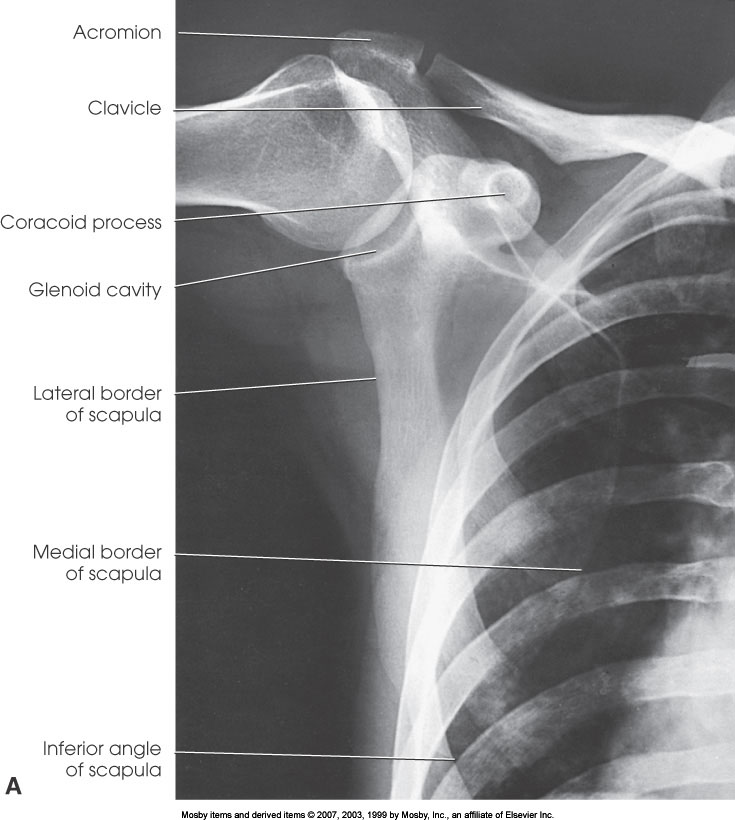

AP Shoulder (External Rotation)

What position is demonstrated?